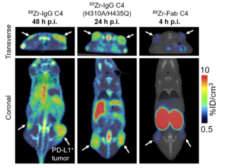

Optimizing immunoPET imaging of tumor PD-L1 expression